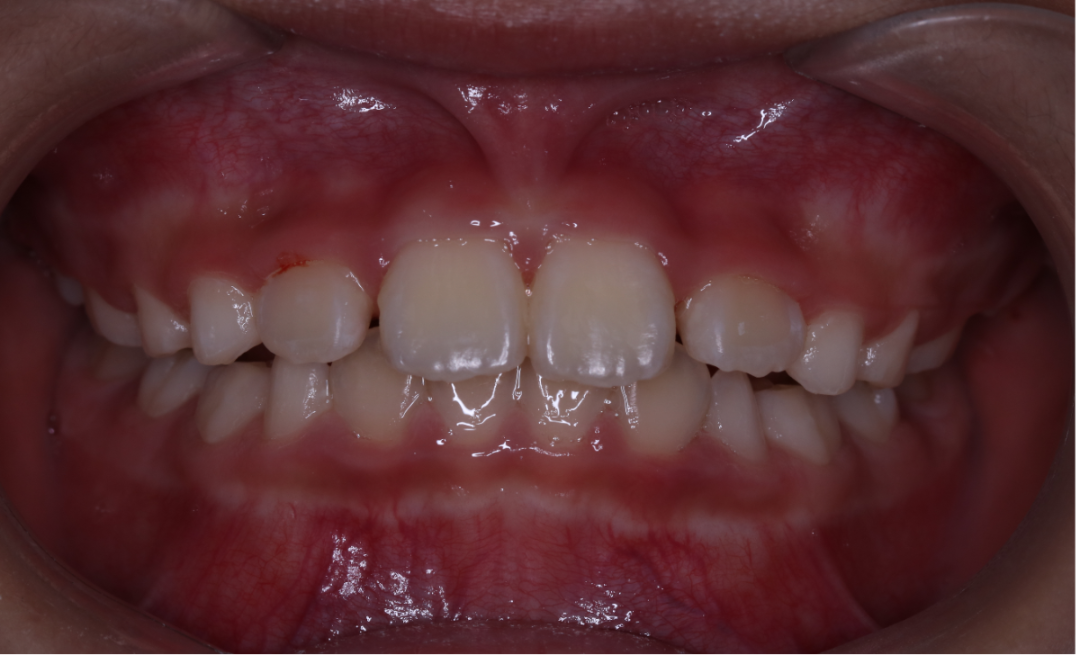

3、一般矫治。根据不同牙颌面畸形选用各类矫治器,一般矫治是口腔正畸矫治中最多见的。如可摘矫治器、功能矫治器、固定矫治器等。近年来,无托槽隐形矫治技术因其美观、舒适的优势渐渐得到人们的青睐,随着口腔正畸医疗技术及材料的不断发展,无托槽隐形矫治技术越来越成熟。目前,大部分错颌畸形可通过无托槽隐形矫治技术纠正。

金属自锁托槽矫治技术

治疗前                        治疗后

无托槽隐形矫治技术

儿童错合畸形早期矫治是阻断影响儿童颌骨、牙齿正常发育的因素,促进颌面部正常发育,降低II期矫正的难度,减少II期矫正的时间,甚至不需要II期矫正。让孩子早期获得自信,绽放灿烂笑容。

术前→术后